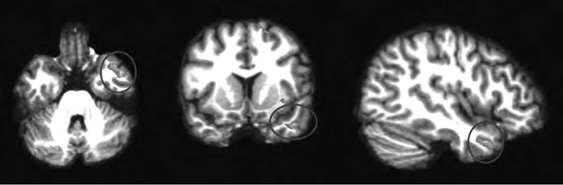

Анализируя далее научную литературу, мы пришли к выводу, что процесс поведенческого подражания с участием верхних отделов височной коры и эмоциональный (физиологический) резонанс, требующий участия островка, тоже имеют отношение к системе зеркальных нейронов. При подражании верхние отделы височной коры кодируют сложные процессы сенсорных следствий двигательных актов; при эмоциональном резонансе островок осуществляет физиологический и аффективный сдвиг, имитирующий его у другого человека. Исходя из параллелизма этих функций реципрокного действия (имитационной, физиологической и аффективной), мы можем использовать термин «резонансный контур», подразумевая, что в нем могут участвовать зеркальные нейроны, но не все компоненты этого контура двигательные, поэтому формально мы не можем назвать такой контур зеркальным. В нашем обсуждении мы примем во внимание это отличие и будем называть резонансный контур именно так, или будем прибегать к выражению «области, связанные с системой зеркальных нейронов» (рис. П.1 и П.2).

П.1

П.2

Рис. П.1, П.2. Функциональная МРТ, выполненная во время выполнения медитации осознавания дыхания. На снимках видна активация верхней височной извилины (рис. П.1) и активация островка и вентрального отдела передней поясной извилины (рис. П.2). Верхняя височная кора, островок и области срединной префронтальной коры (показанные здесь) вместе с системой зеркальных нейронов, как предполагается в тексте, содержат элементы «резонансного контура», которые активируются в ходе внимательного осознавания (снимки напечатаны с разрешения Сары Лазар © 2005)